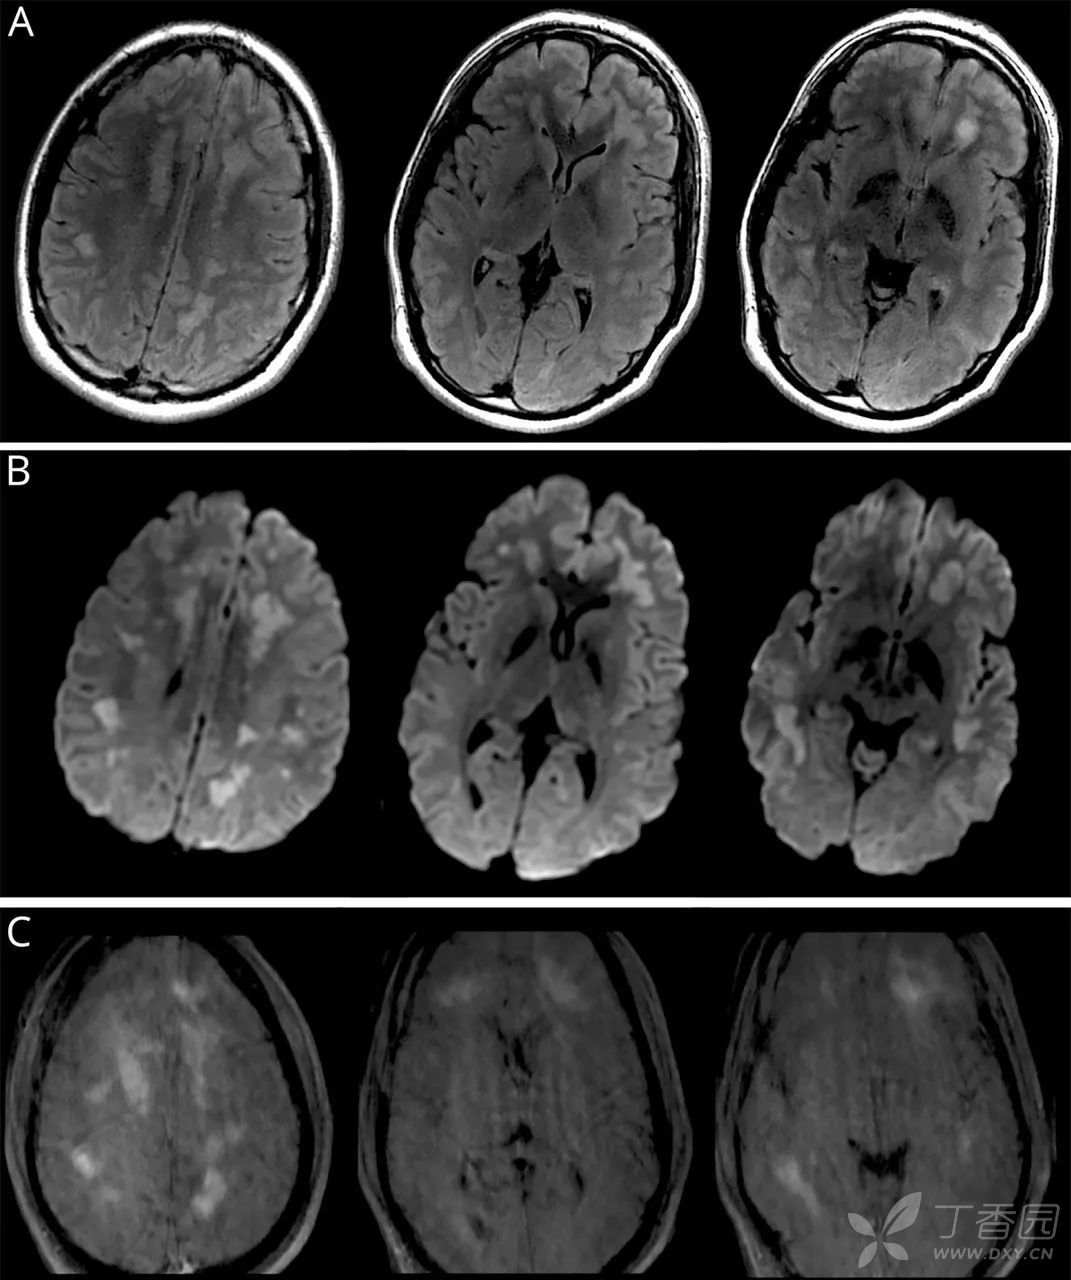

(3)入院第8天进行MRI增强扫描显示皮质下白质卵圆形FLAIR高信号病灶(图A),伴弥散受限(图B)和中度增强(图C)。颅内外血管造影正常。

图 患者发病时的MRI影像结果。轴位T2 /FLAIR图像(A)显示双侧皮层下白质中有多个不规则和卵圆形高信号病灶;DWI(B)显示弥散受限;T1增强(C)显示病灶强化。